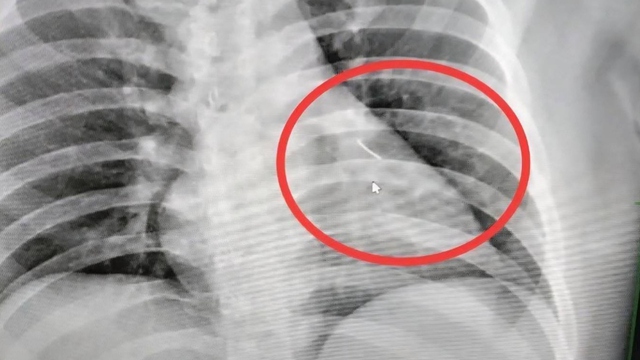

Cây kim được phát hiện trong ngực người đàn ông.

Nhân viên bệnh viện đã chụp X-quang và phát hiện một vật thể nhỏ sắc nhọn bên trong cơ thể ông, gần tim. Vật thể này sau đó được xác định là một cây kim dài khoảng 7 cm. Ông Boonlert sau đó được chuyển đến Bệnh viện Buriram để phẫu thuật, các bác sĩ mô tả ca phẫu thuật này phức tạp và có rủi ro cao.